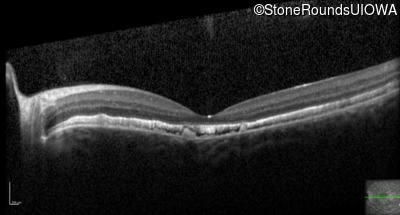

Optical Coherence Tomography - Right - 20/100 sc

Exemplar / OCT Stack

Optical Coherence Tomography - Left - 20/25 -3 sc